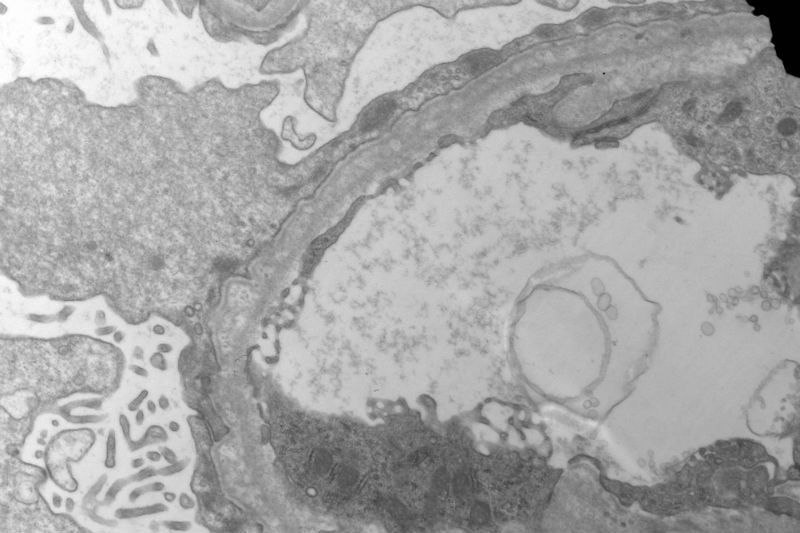

The patient has a long history of "chronic kidney disease". Initially, he did not tell the nephrologist that he started to have kidney disease decades ago. Given the characteristic ultrastructural changes, Alport's syndrome is suggested.

Yes, I agree with your observation that there are a lot of foamy cells. The most impressive change is the lamination or splitting of the glomerular basement membrane.